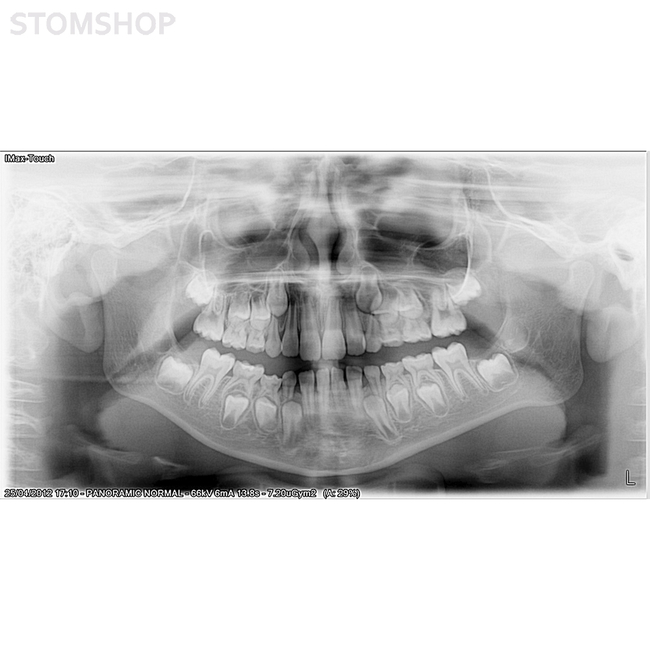

Ортопантомограф I-Max Touch Pano предназначен для получения панорамных снимков челюстей у взрослых и детей. Вывод изображения осуществляется на монитор, экран пульта и на флеш-карту. Значительное уменьшение дозы рентгеновского излучения. Полностью компьютеризированное управление. Без цефалостата.